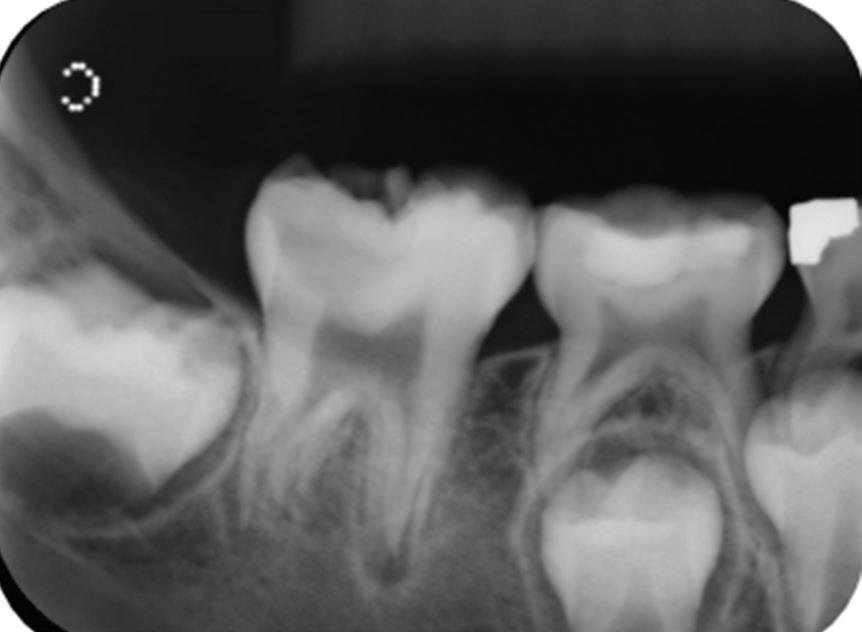

A healthy 10-year-old boy, accompanied by his mother, sought treatment of his mandibular right first molar because of pain in response to cold stimuli but reported no spontaneous pain in this tooth. Clinical examination revealed a carious lesion involving the occlusobuccal surfaces, and the tooth also appeared hypomineralized on the affected surfaces (Fig 1). The tooth responded positively to sensitivity tests, including the electric pulp test and cold test (Endo-Frost, Coltene), and there was no lingering pain or pain on percussion. A preoperative radiograph showed a large carious lesion extending to the pulp, incomplete root formation, and no pathologic periapical lesions (Fig 2). Therefore, the initial preoperative diagnosis was reversible pulpitis. The patient and parent were informed of possible pulp exposure, and VPT treatment after pulp exposure was explained in detail. Written consent for VPT was obtained from the parent.

deep caries, exposed pulp, and incomplete root formation but no pathologic periapical lesion.

Fig 2. Preoperative radiograph showing